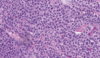

Quel groupe de tumeur représente la très grande majorité des cancers du testicule ?

Tumeurs germinales (> 90%)